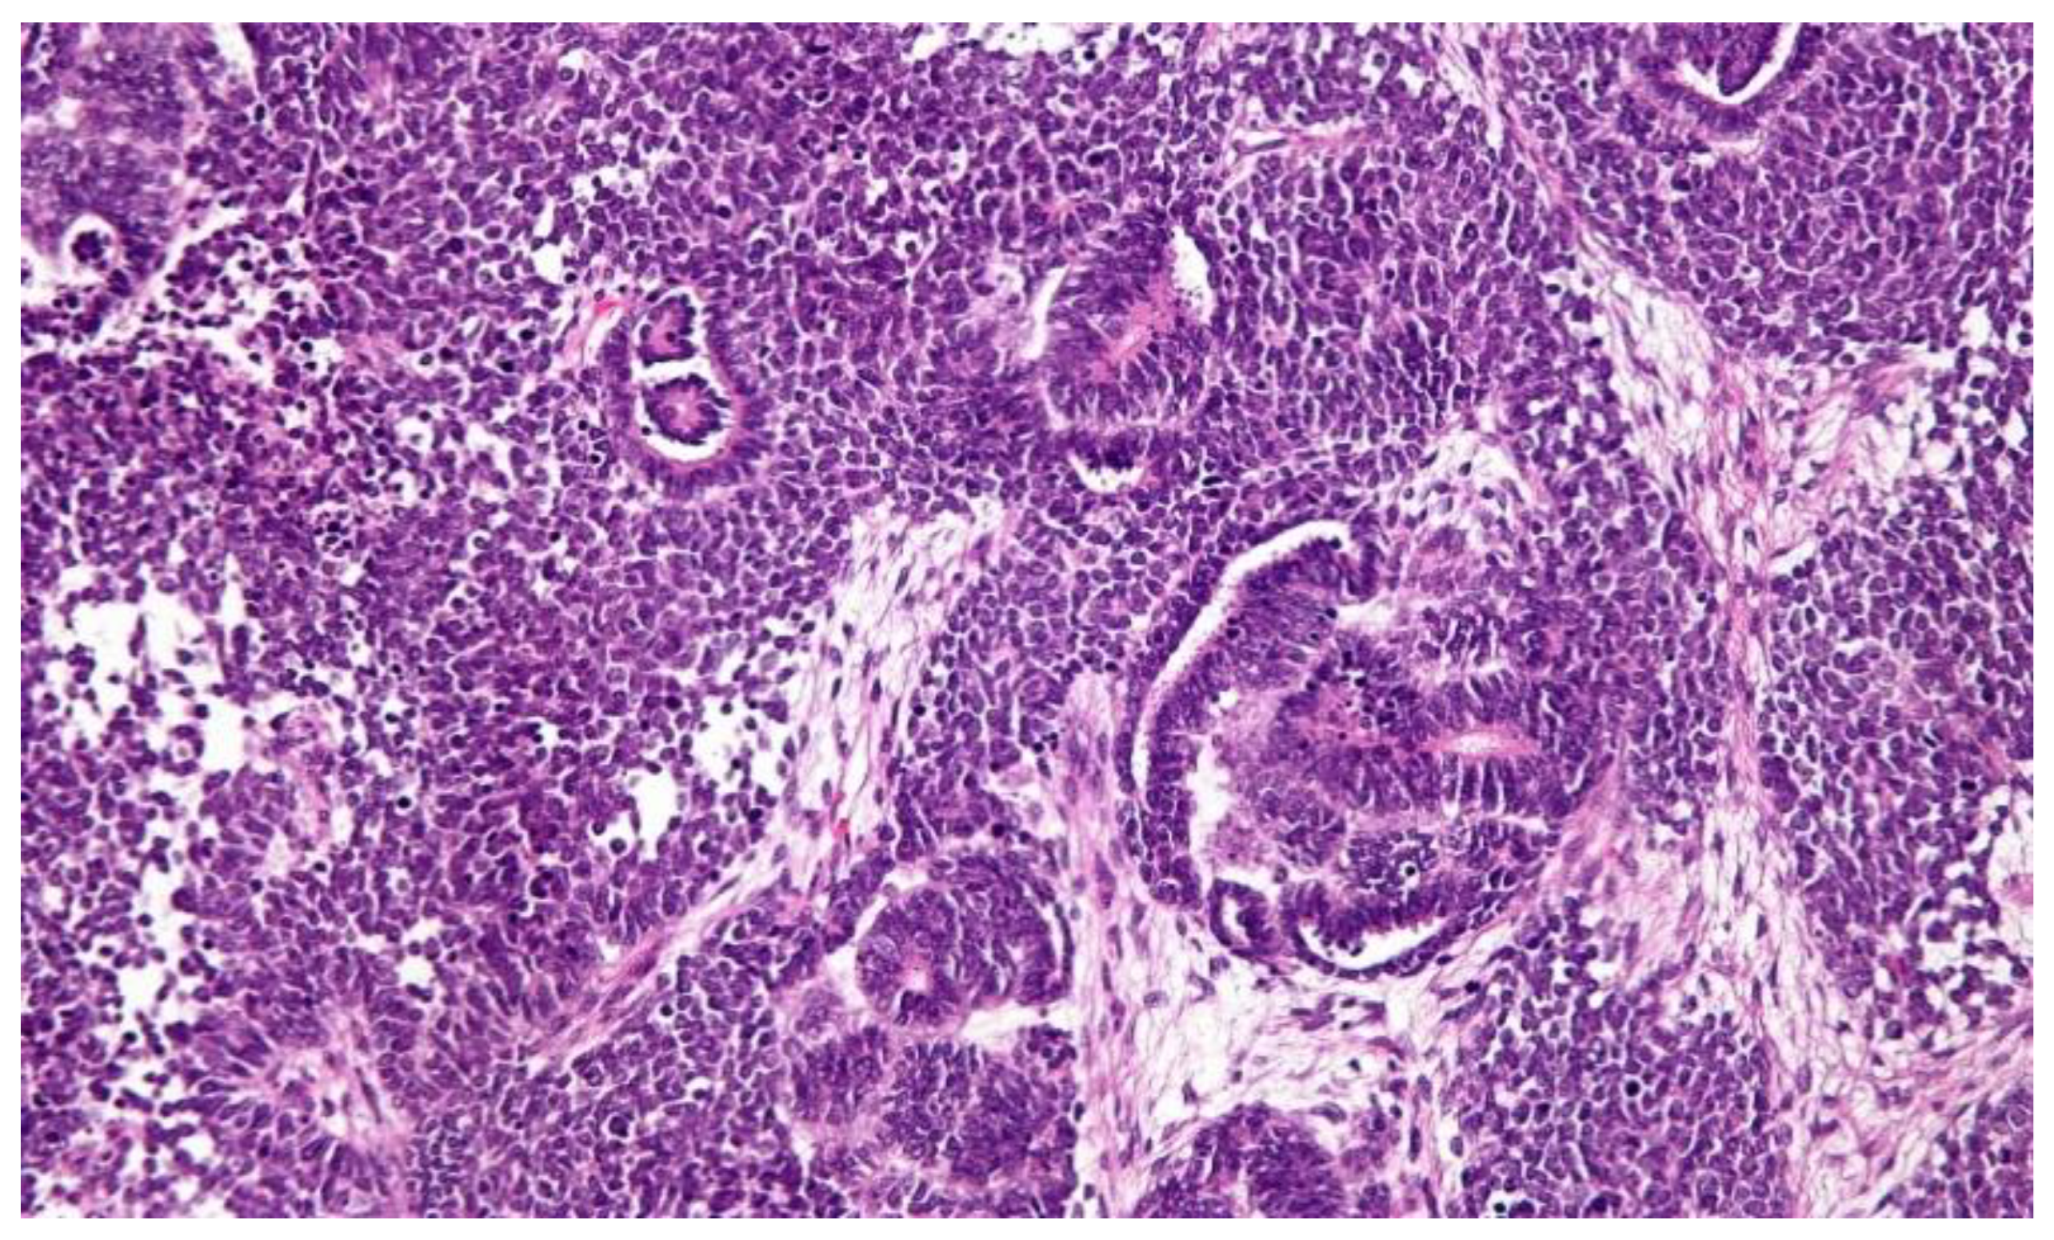

1.2. Pathology

- Popov, S.D.; Sebire, N.J.; Vujanic, G.M. Chapter 1—Wilms’ Tumour—Histology and Differential Diagnosis. In Wilms Tumor; van den Heuvel-Eibrink, M.M., Ed.; Codon Publications: Brisbane, Australia, 2016. [Google Scholar]